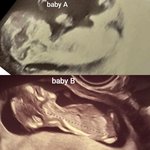

Dnes jsem 11dpo. Teat neni z ranni moci. Test Pepino. Bolava prsa, taha podbrisko. Zkouseli jsme podle ovu testu, tak proto jsem strasne zvedava jesli to vyslo. Fotka upravena, protoze nazivo mam poci